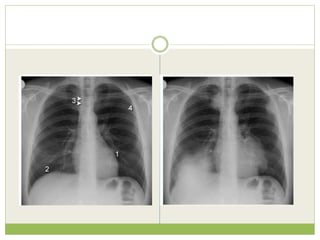

The clinical question

Clinical information provided

๏‚— Recent increase in shortness of breath

๏‚— No fever or productive cough

๏‚— Left shoulder and arm pain

๏‚— Heavy smoker

๏‚— Weight loss

Findings

Left apical shadowing

Raised left hemidiaphragm

Increased extra-thoracic

soft tissue density (*) with

displacement of the

scapula on the left

(arrowheads) - compare

with right

๏‚— Interpretation in view of clinical details

๏‚— Cancer - Smoker with weight loss and left apical

consolidation/mass and no clinical features of

infection

๏‚— Phrenic nerve palsy - Increased shortness of

breath and raised left hemidiaphragm

๏‚— Brachial plexopathy - Arm pain and axillary soft

tissue swelling